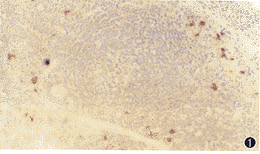

DC主要分布在淋巴结皮质滤泡间和深层副皮质区,围绕淋巴滤泡分布,个别散在于髓质中(图1)。DC体积较大、被染成棕黄色,细胞核及细胞质均着色。胞体形状不规则,向外伸出长短不等的突起,伸入到周围淋巴细胞之间。细胞核较大、肾形,一侧向内有切迹,色浅、核膜清晰(图2)。

图1 分布于副皮质区滤泡周围的树突状细胞。免疫组化SABC法×115